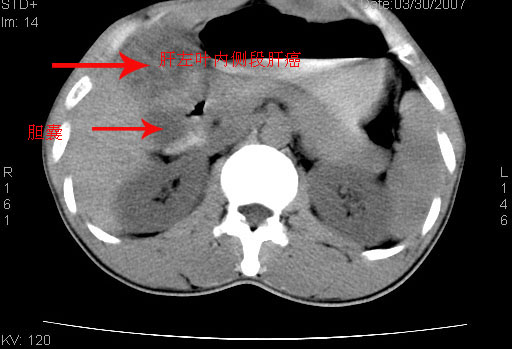

患者 、男性、32岁。病史:小三阳病史5年余。右肋胀痛半年余。

超声检查:肝右前叶可探及大小约58mmx58mm稍强回声反射,轮廓清,形态规则,cdfi:周边及内部可见点状血流信号。

ct:肝右叶前段可见团块状混杂密度影,大小约58mmx58mm,腹膜后可见肿大淋巴结。该患者拒绝增强。请会诊!明天予穿刺明确诊断.ct诊断意见:肝右叶前段肝癌并腹膜后淋巴结转移。